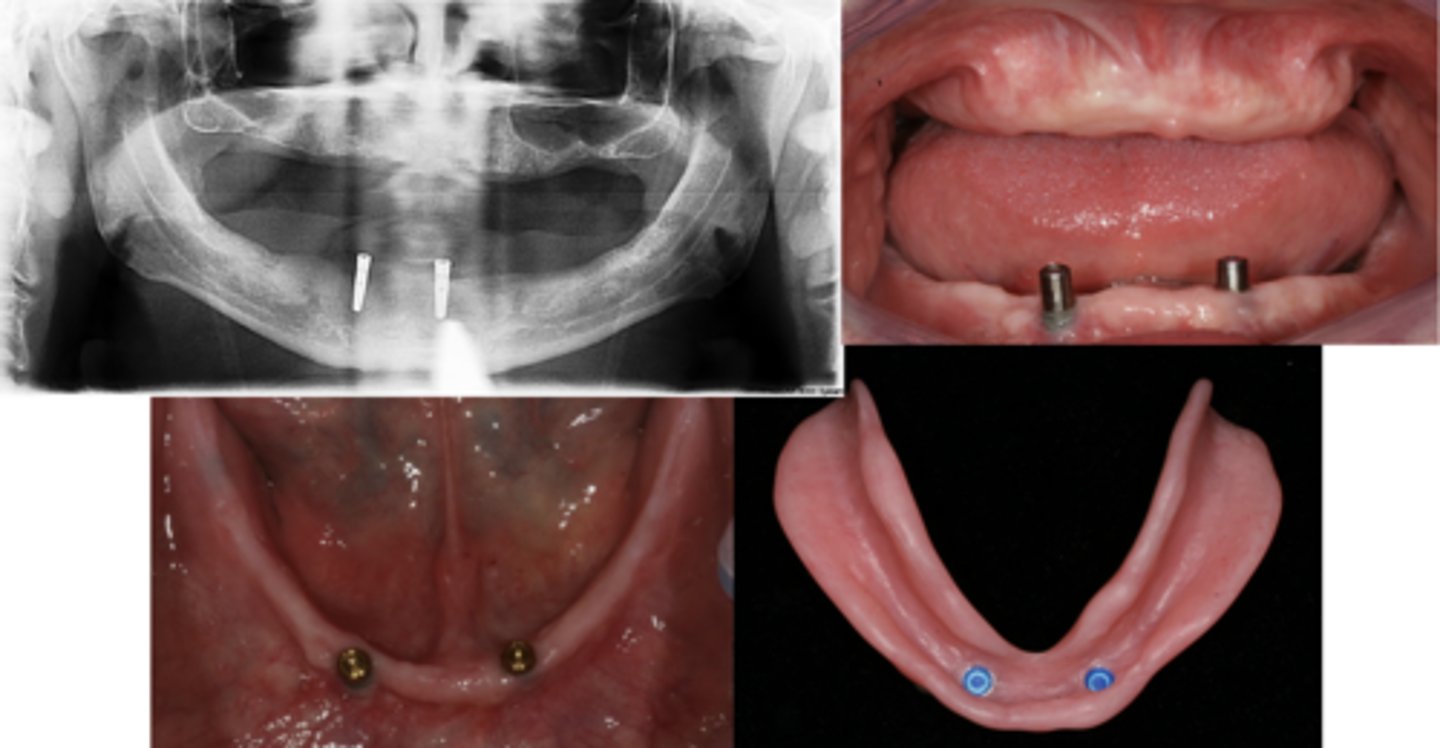

Implant-assisted removable complete denture

What are these images showing?

2-implant overdenture

The evidence currently available suggests that restoration of the edentulous mandible with a conventional denture is no longer the most appropriate first choice prosthodontic treatment.

There is now overwhelming evidence that a _________ should become the first-choice treatment for the edentulous mandible

T/F: Whilst it is accepted that the two-implant overdenture is not the gold standard of implant therapy, it is the minimum standard that should be sufficient for most people, taking into account performance, patient satisfaction, cost and clinical time.